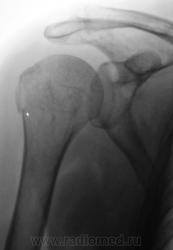

Травма.   Пациентка направлена на рентгенографию плечевого сустава.

Давно любимый вколоченный перелом х/шейки.